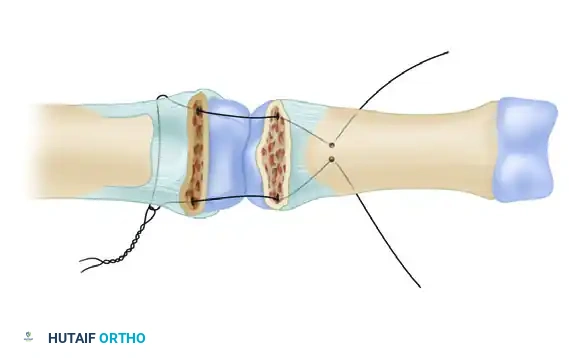

- Large Single Fragment (>50% Articular Surface): If a large, single volar fragment involving more than 50% of the joint surface is present, ORIF is indicated. Fixation can be achieved with one or more K-wires, minifragment screws, or a wire loop pullout technique.

- Small Fragments (<50% Articular Surface): If the fragment or fragments include less than 50% of the articular surface, the technique described by McElfresh, Dobyns, and O’Brien is preferred. This utilizes an extension block splint, allowing active flexion of the PIP joint while preventing the terminal extension that leads to dorsal subluxation. This gives satisfactory results, especially in cases without gross displacement.

- Chronic/Persistent Subluxation (≤40% Articular Surface): For persistent dorsal fracture-dislocations with preserved condyles of the proximal phalanx and a volar defect of 40% or less, the volar plate arthroplasty method of Eaton and Malerich may be used. They reported successful use of this technique in old, healed, displaced fractures even 2 years after injury.

An alternative, highly advanced treatment involves the reconstruction of the middle phalanx volar lip using an autogenous osteoarticular graft.

A size-matched segment of the distal hamate articular surface is carefully shaped to match the comminuted contour of the middle phalanx. The distal hamate (articulating with the base of the 4th and 5th metacarpals) possesses a central ridge that perfectly mimics the median ridge of the middle phalangeal base, providing exceptional coronal plane stability.

Figure 67-49A: Persistent dorsal PIP joint subluxation with a nonreconstructible middle phalangeal volar lip fracture.

Figure 67-49B: Volar exposure of the middle phalangeal base and geometrical preparation of the defect to receive the graft.

Figure 67-49C: Intraoperative fluoroscopic view of the distal hamate donor site.

Figure 67-49D: Fixation of the hemi-hamate graft with two minifragment screws to replicate the middle phalangeal base concavity.

Figure 67-49E: Radiograph demonstrating a concentric joint without collapse or dorsal subluxation at 2 years after surgery.